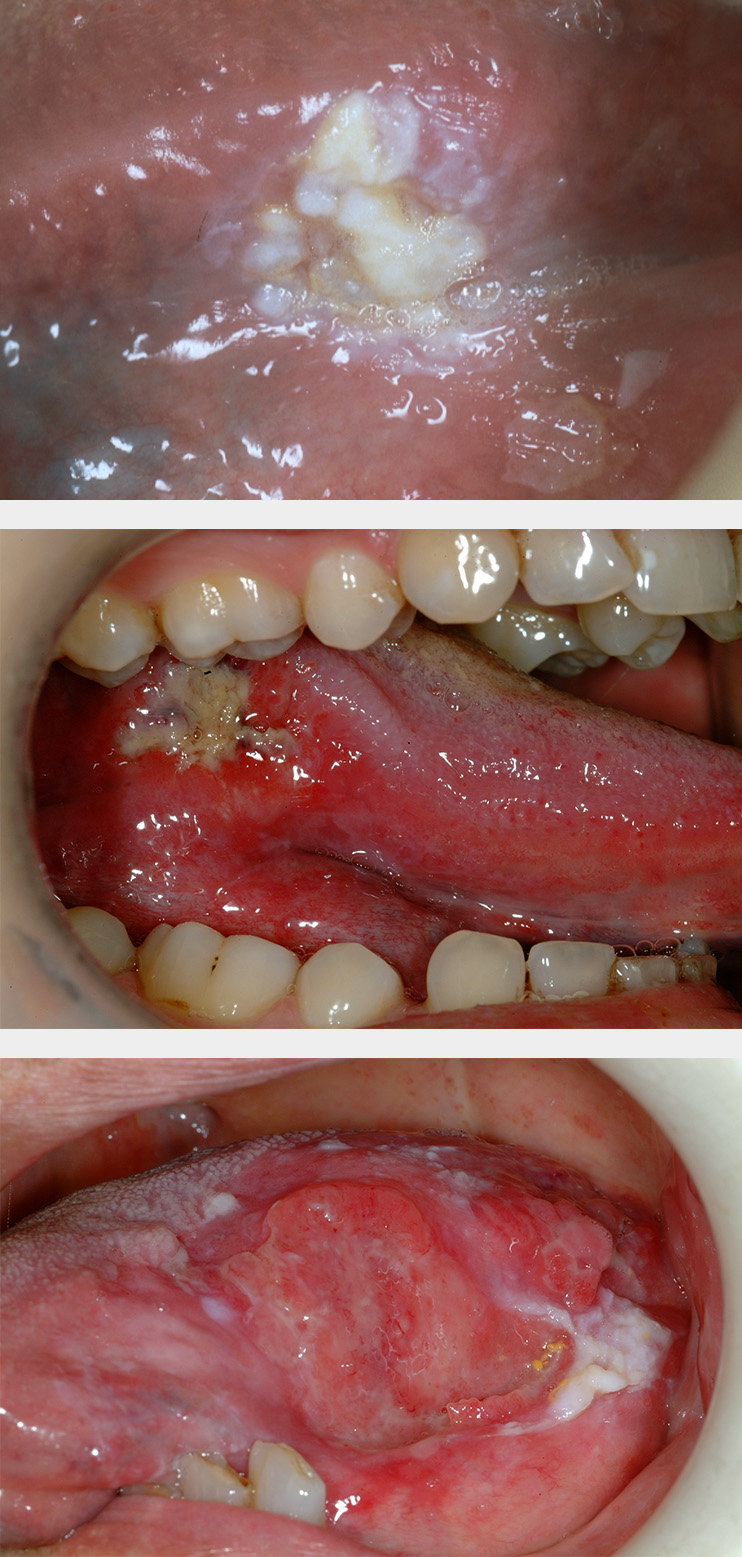

Erythroplakia is defined as a red patch (see Figure 2) that cannot be diagnosed as any other lesion. Erythroplakia is less common than leukoplakia but tends to display more severe degrees of dysplasia as well as a higher overall risk of malignant transformation; the overall risk has been quoted as 14 to 67 % (see below), and approximately 40 to 50 % of erythroplakic patches have high-grade dysplasia or carcinoma in situ present. The most common sites for erythroplakia are the floor of the mouth, tongue and soft palate.

Erythroleukoplakia (also known as speckled leukoplakia) is the third of the oral mucosal lesions commonly associated with a risk of malignant transformation (see Figure 3). Speckled leukoplakia is an intermediate risk for malignant transformation.

Lichen planus is a chronic autoimmune disorder of the skin and often affects the oral mucosa as well. It usually shows characteristic streaks or strands of white keratosis (see Figure 5). Lichen planus is sometimes associated with epithelial dysplasia, a so called lichenoid dysplasia. Of the fairly low malignant transformation risk (the incidence is approximately 1 to 3 %), the majority of cases is due to lichenoid dysplasia. It is important to note that the real risk of transformation of lichenoid dysplasia and erosive lichen planus warrants intervention whereas reticular pattern lichen planus that is symptomless doesn’t need anything in the way of intervention. This is fortunate given how common that condition is.